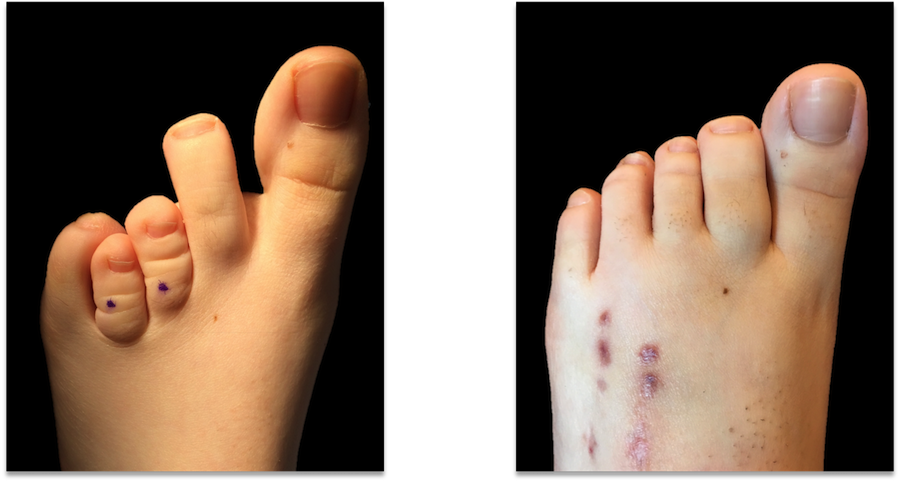

Another case pre operative picture on left , postoperative ( 10 weeks later) on right with minimal scarring. In this case we also corrected a mild bunion deformity hence the scar over big toe joint.